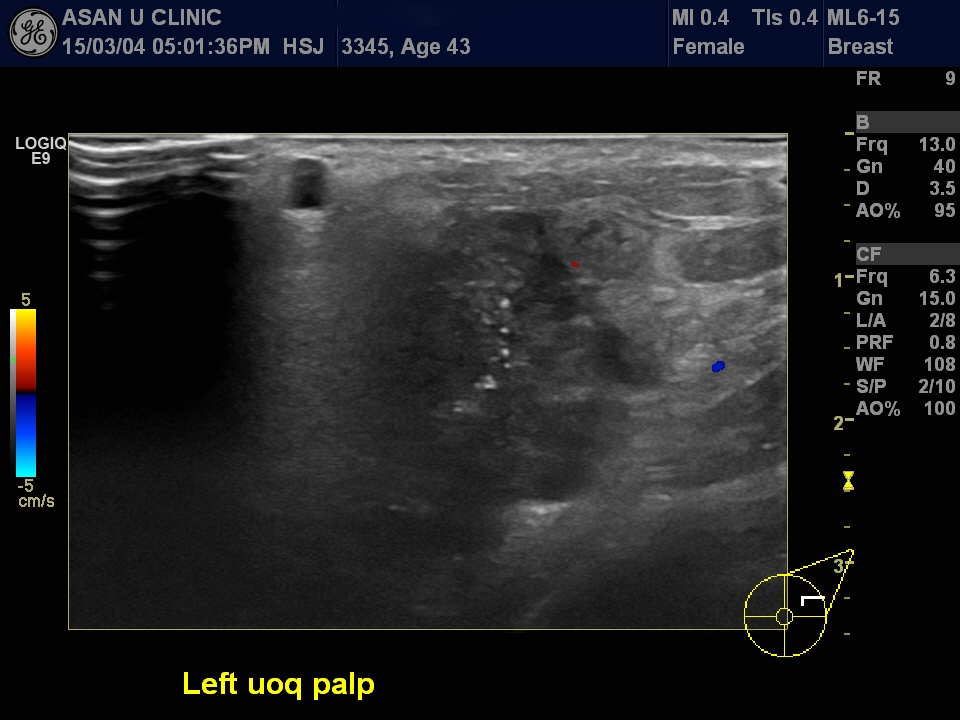

43세 여성.

좌측 유방에 갑자기 만져지는 혹으로 내원.

겨드랑이에도 림프절전이가 의심되었음.

유방의 몽우리 조직검사 및 겨드랑이 림프절 세포검사====> 침윤성 유관암의 좌측 액와전이